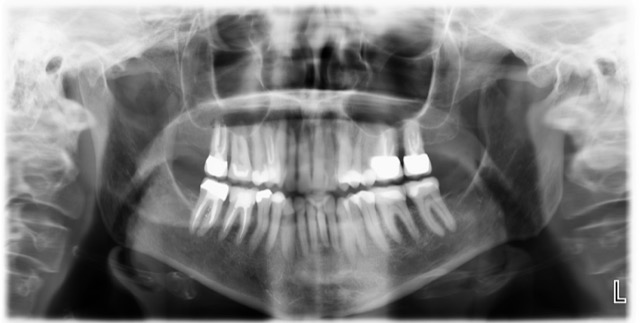

Ik heb nog een aantal afbeeldingen van de scan online gezet, en een overzichtsfoto, die een paar maanden na de WKB is gemaakt. >>http://3dscan.jalbum.net/x-ray-scan/<<

Daarmee is ze naar de kaakchirurg geweest omdat de tandarts dacht aan een kaakholte ontsteking. Hoe dit verder is verlopen moet ik ook even op een rijtje zetten.

de foto's zijn van okt/nov 2020 en de cbct van juni 2021.

Welke kroon is als laatste geplaatst?. Als het de 16 is dan zou ik op basis v d tweede foto zien dat aan een v d mesiale ( voorste wortel) een ontsteking is. Excuseer als ik het fout zie, ik moet het doen met wat u mij levert. Wortelpunt v d 14 is voor mij ook verdacht. Koud en warm alleen in die kies of meerdere, dat is verwarrend maar kan verklaard worden doordat een kanaal "dood" is en de andere nog niet. Ik zou in de 16 proefboren zonder verdoving. Als er geen gevoel in is dan een wortelkanaal behandeling. Maar als er toch gevoel in zit geeft dat geen uitsluitsel. Ik zou beginnen met een WKB in de 16. U bent overal geweest zegt u. Wat was het oordeel v d endodontoloog.

Ik ben nu bij een andere tandarts en hij heeft mij doorgestuurd naar een endodontoloog. De nieuwe tandarts zegt dat er niets met mijn gebit is. De endodontoloog bevestigt dat en zegt dat ik last heb van sensitisatie/neuropatische pijn. Het gaat om kies 15. De pijn zit nu in alle elementen, echte zenuwpijn. Omdat ik niet tegen de medicijnen kan is mij verteld dat ik ermee moet leren leven. Ik zie zelf dat het tandvlees rondom de nieuwe kroon rood en dik is, dat was nooit zo. Voor mijn 'zicht' is de kroon ook te groot maar blijkbaar zijn de contactpunten goed. Toch zegt mijn gevoel dat het daar niet klopt, anders zou het tandvlees niet dik zijn.